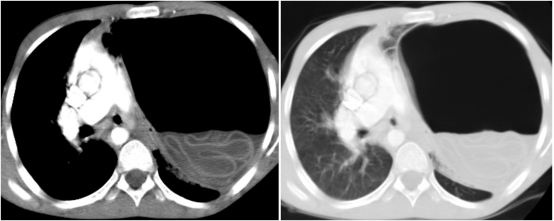

增强胸部CT扫描证实左侧大量气胸、纵隔向右移位,并可见"漩涡征"(图2)。诊断为包虫囊壁破裂导致张力性气胸。

图2 CT图像显示左侧张力性气胸、纵隔向右侧移位以及“漩涡征”的存在。